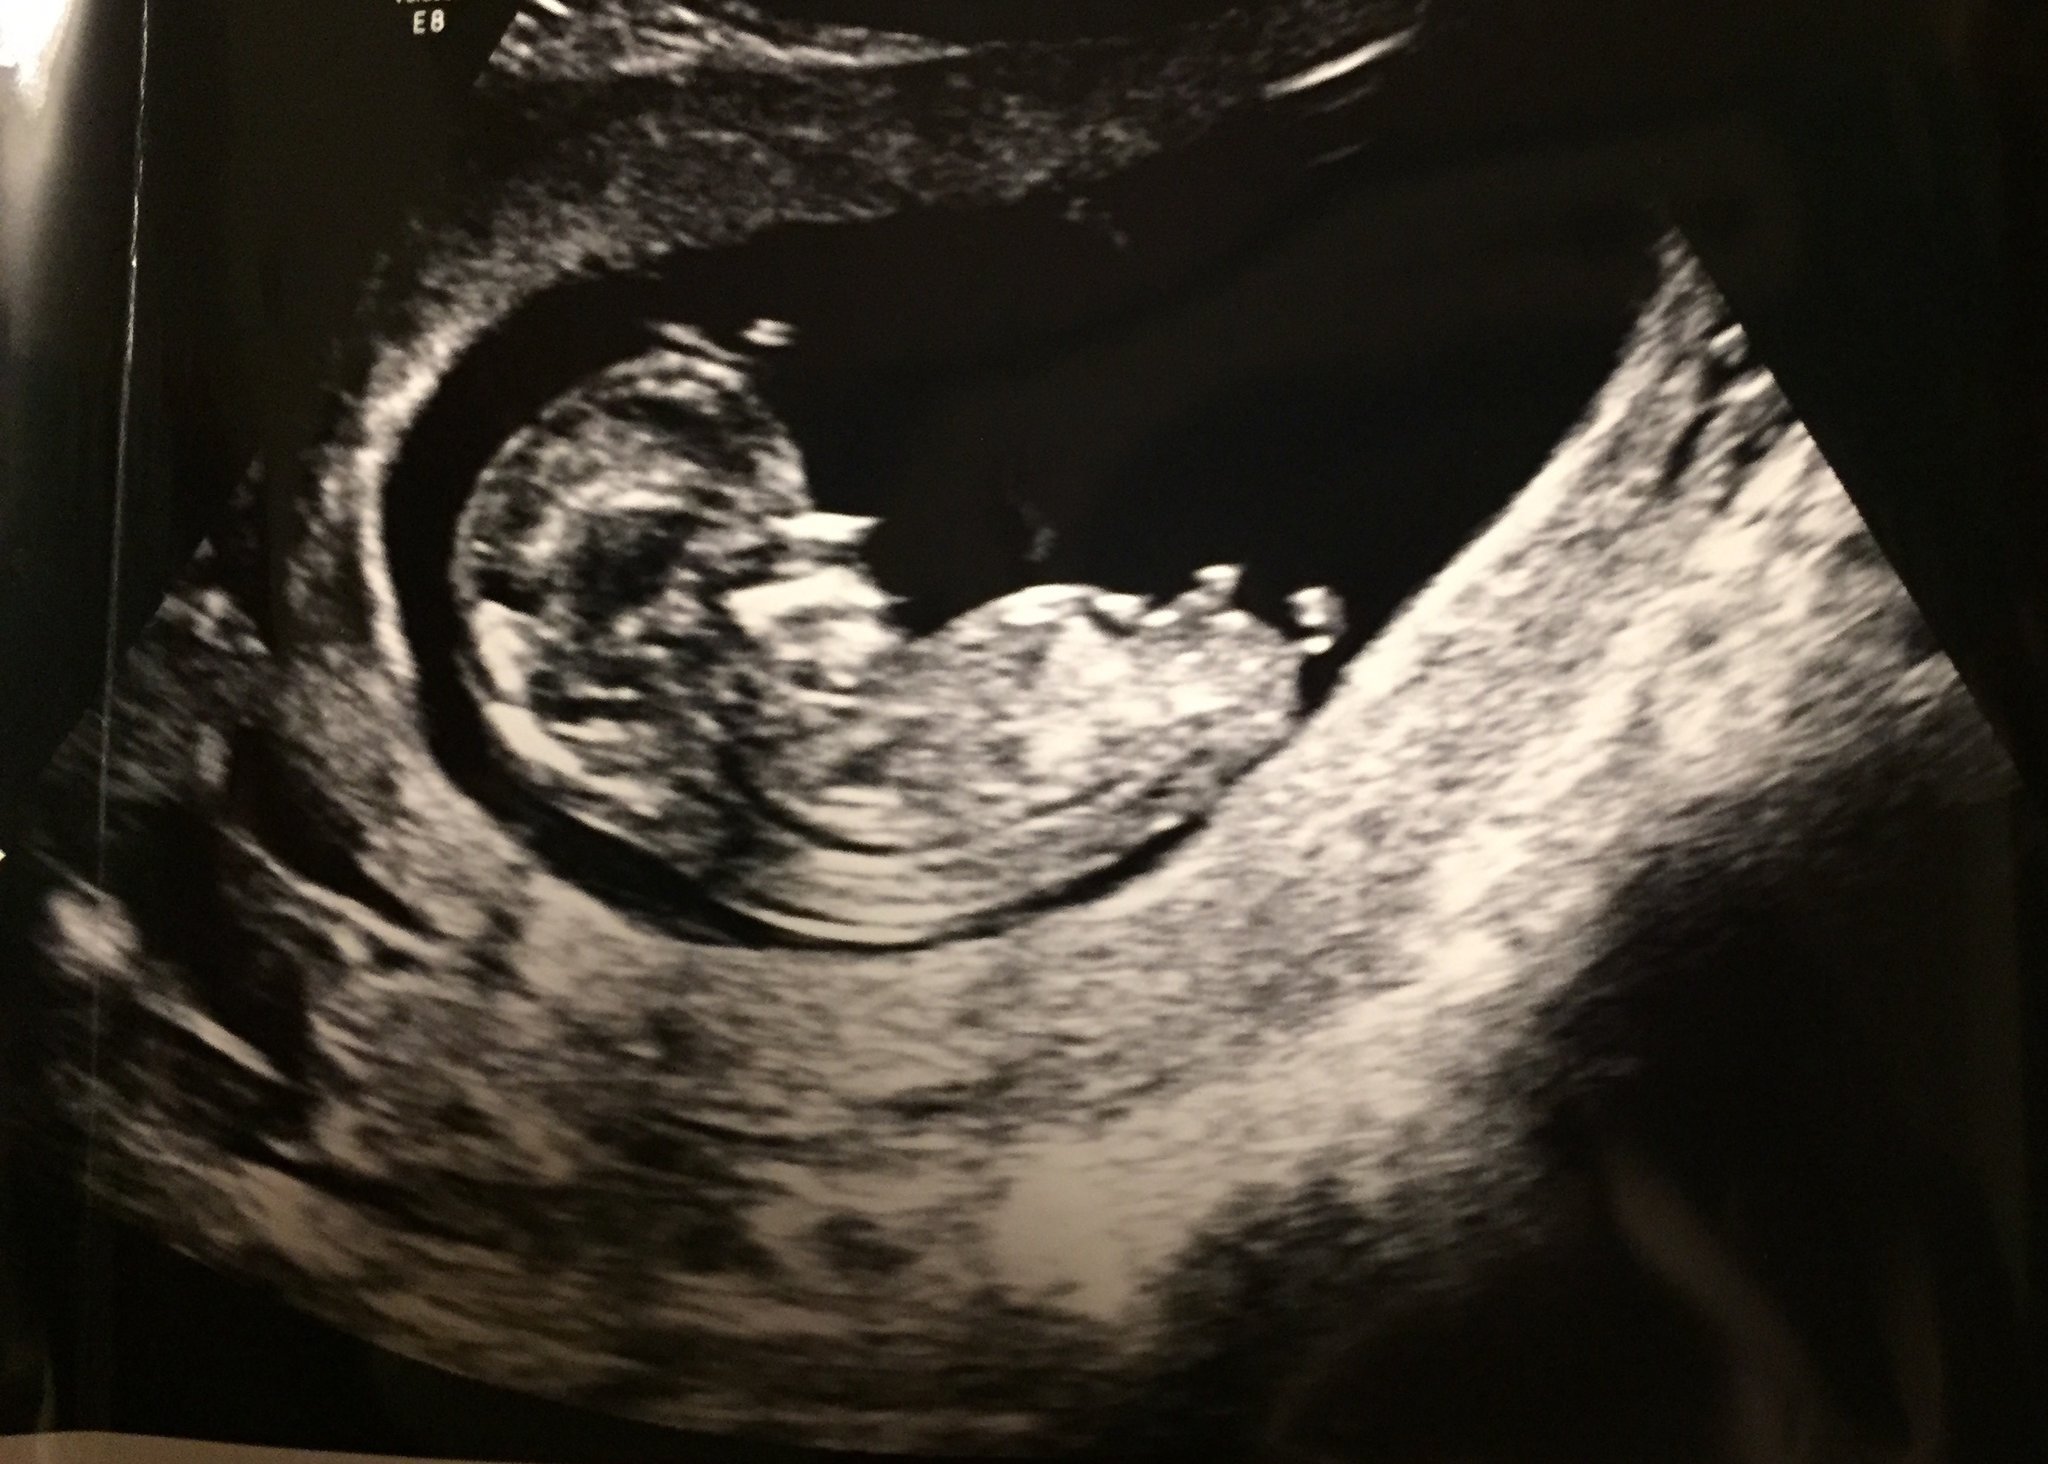

We had a early gender ultrasound yesterday! We went in and the tech told us if I wasn't measuring 13 weeks they wouldn't be able to tell us what the sex was. I got a little nervous because I am only 12+5 and we live an hour away from where we went to get this done. So as I'm laying on the bed she is measuring the baby, and I'm trying to see if I can guess what the baby is. The tech then says that I'm measured at 13+1, so I get super excited! She then says I already know what the gender is. My face lights up when she says....ITS A GIRL!

We we are so beyond happy that we will be welcoming a baby girl into our family! I can't wait for my son to be a big brother to his sister !